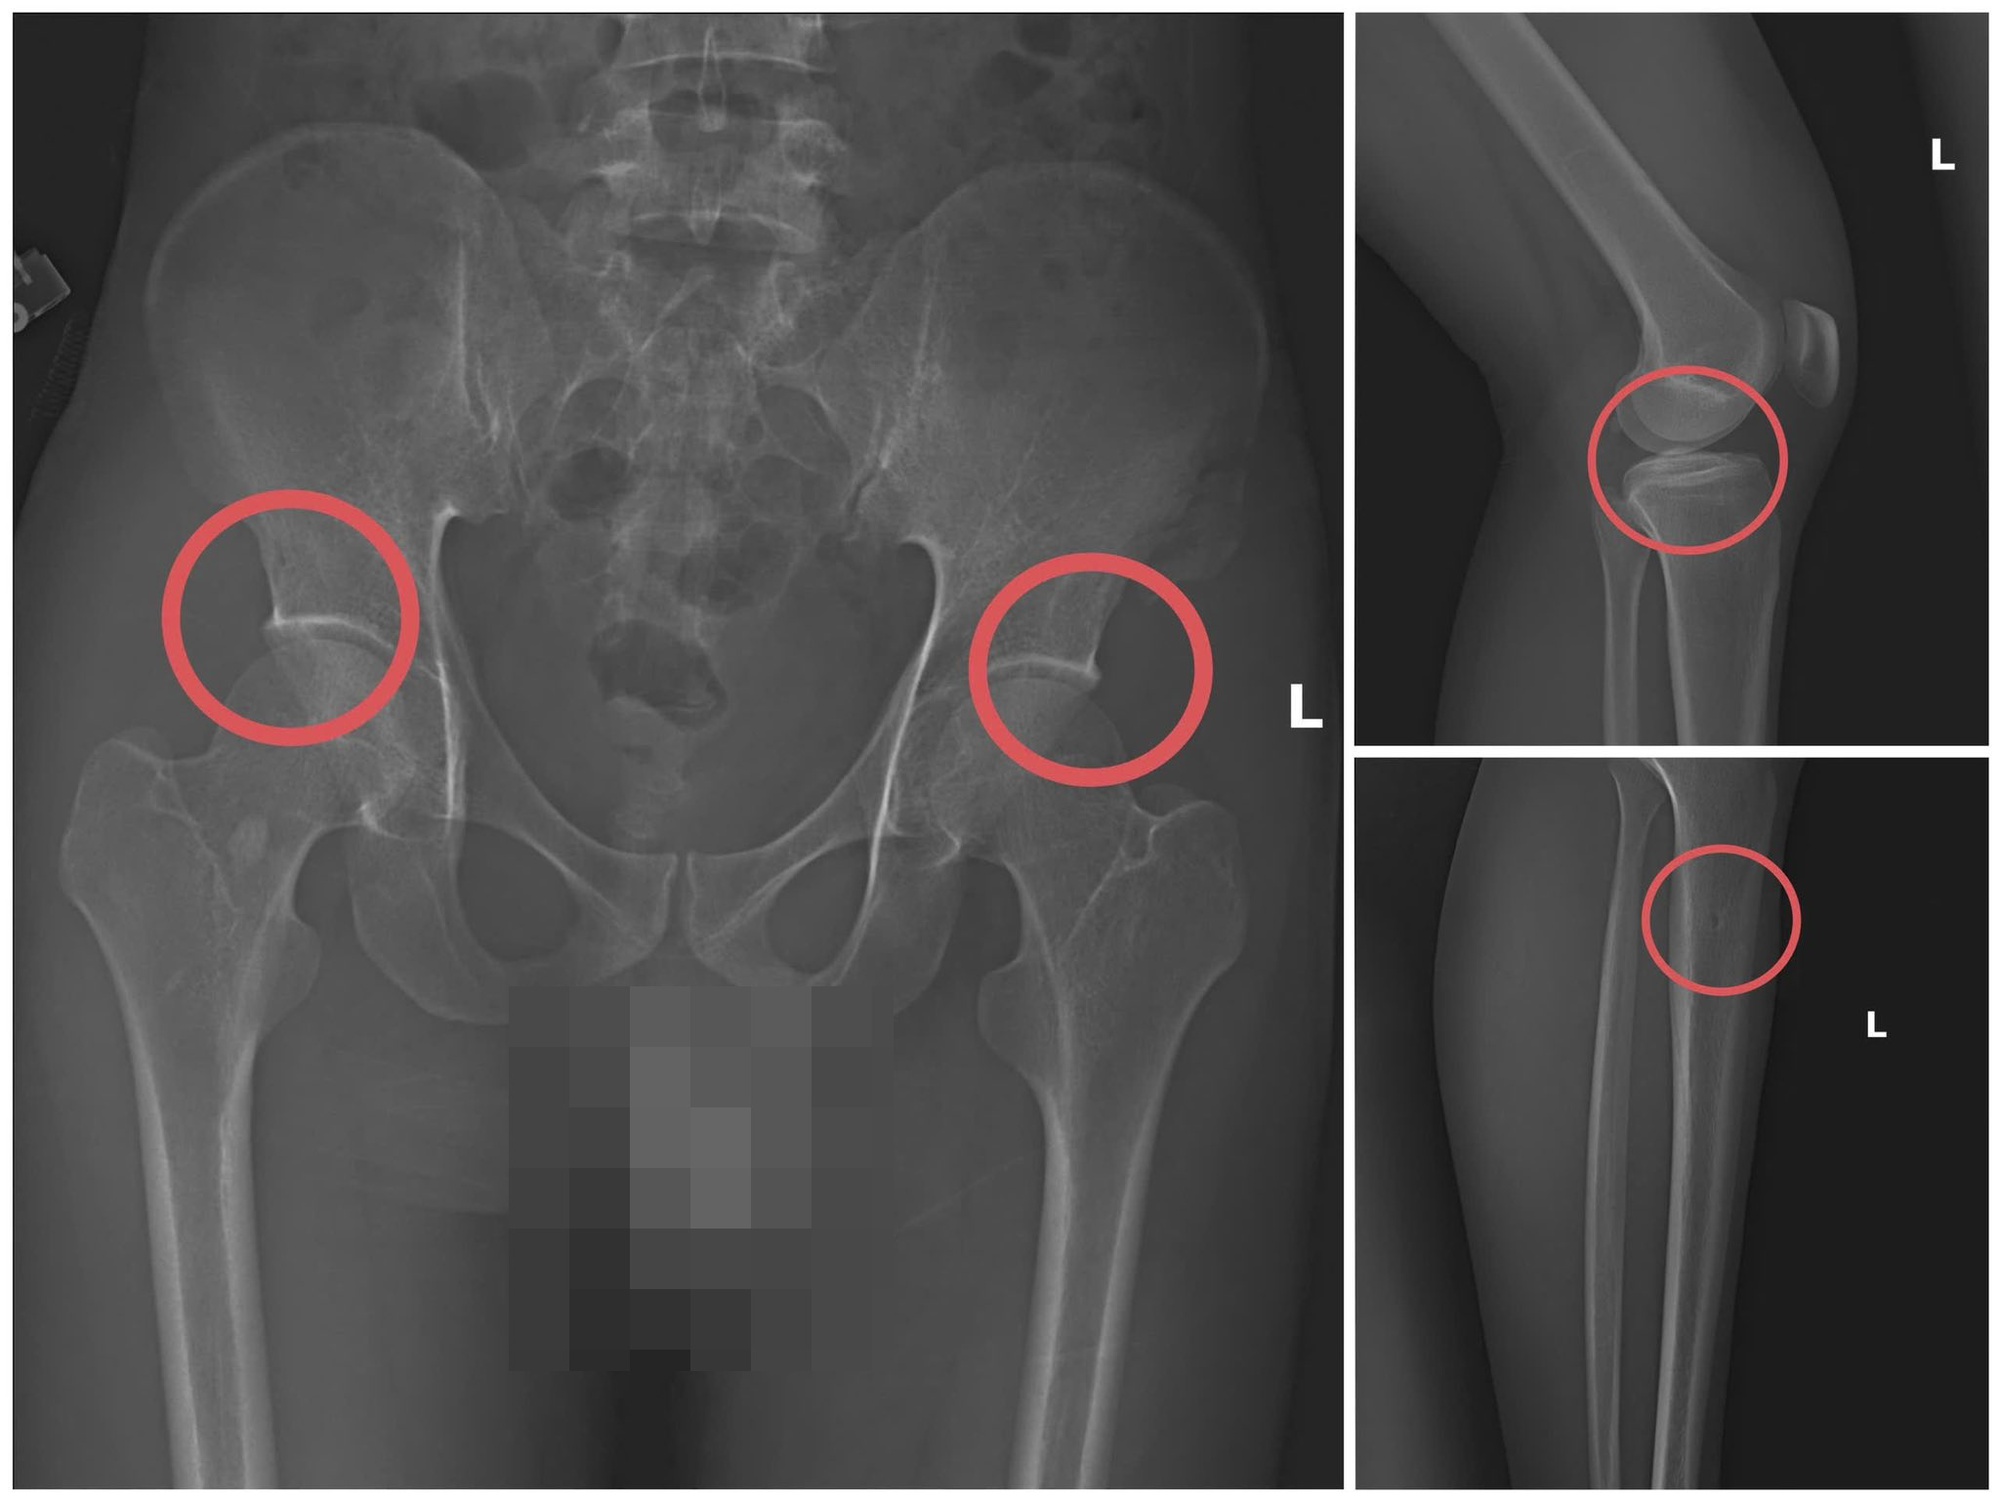

Hình ảnh xương khớp do Châu gây thương tích để chiếm đoạt tiền bảo hiểm nhân thọ – Ảnh: Công an tỉnh Phú Thọ

Đáng chú ý, Châu trực tiếp thực hiện hành vi tiêm thuốc mê, rồi dùng kim tiêm, búa, đinh để tác động vào xương người mua bảo hiểm, tạo nên các vết nứt, vỡ xương tương tự tai nạn thật. Khi thương tích đã tạo xong, Châu tiếp tục hướng dẫn các đối tượng dựng hiện trường giả như điện giật ngã, trượt chân ngã suối nhằm hợp thức hóa bệnh án và hoàn thiện hồ sơ yêu cầu chi trả.

Theo đó, thông qua các tài liệu thu thập được, cơ quan Cảnh sát điều tra làm rõ đối tượng Tạ Minh Châu (SN 1995, nguyên cán bộ Trung tâm Y tế huyện Cẩm Khê) là kẻ chủ mưu, cầm đầu. Lợi dụng thời gian dài công tác trong ngành y và am hiểu sâu cấu tạo xương – khớp, cũng như cơ chế chi trả bảo hiểm đối với các thương tích gãy xương giá trị cao, Châu đã dựng lên một quy trình trục lợi bài bản, từ việc vận động mua bảo hiểm, tổ chức gây thương tích, đến hợp thức hóa hồ sơ bệnh án để chiếm đoạt tiền của các công ty bảo hiểm.